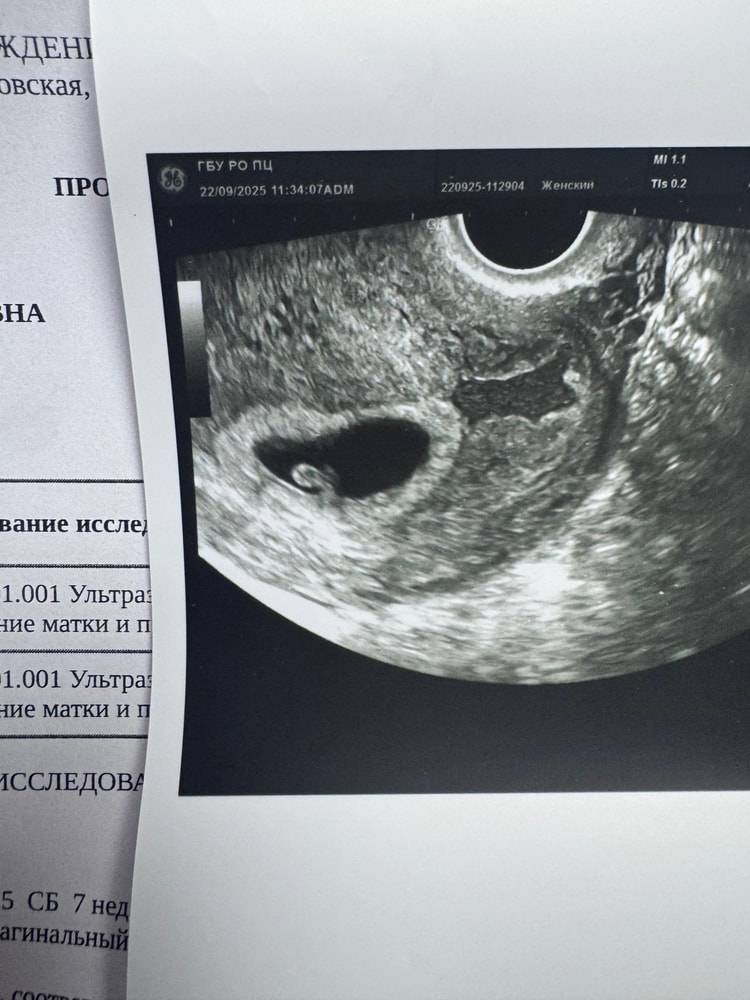

центр новый , врачи доброжелательные, посмотрели на узи и на кресле , успокоили ! Да,есть гематома , но она средних размеров,отслоек нет,боли и крови тоже , пока просто половой и физический покой + если будут боли, то нужно будет свечи вставлять , дали направления на анализы , повторный прием у врача теперь 8 октября ❤️

Сегодня прям поближе рассмотрела крошку , я в шоке , там мини человек растет !

по ктр срок 6+3